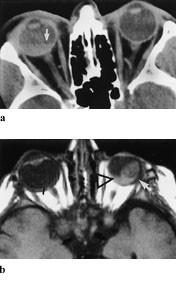

Ved mistanke om retinoblastom utføres først oftalmoskopi og ultralydundersøkelse. Hvis ultralydundersøkelsen ikke viser kalk, bør CT gjøres (fig 3). Hvis ultralydundersøkelse eller CT viser kalk, bør MR utføres for å avgjøre om det er ekstraokulær utbredelse av tumor (fig 4), samt vise dette i forhold til n. opticus og orbita (5). Ved bilaterale eller familiære retinoblastomer er MR indisert for å utelukke eller påvise asymptomatisk midtlinjemalignitet, såkalt pinealoblastom (6).